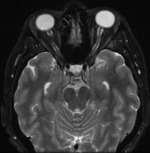

W badaniu neurologicznym wykonanym przy przyjęciu na oddział nie stwierdzono odchyleń od stanu prawidłowego, poza zgłaszanym przez pacjentkę dwojeniem przy spojrzeniu na wprost i w prawo. Wykonano rezonans magnetyczny (MR) głowy z kontrastem, który wykazał objaw częściowo pustego siodła tureckiego (ryc. 1). W MR odcinka szyjnego kręgosłupa uwidoczniono cechy umiarkowanej spondylozy szyjnej, bez zmian pourazowych. W rezonansie magnetycznym oczodołów wykazano natomiast cechy nadciśnienia śródczaszkowego pod postacią zwiększonej ilości płynu w pochewkach nerwów wzrokowych oraz obrzęku tarcz, z poszerzeniem zbiornika nadsiodłowego (ryc. 2, 3).

Rycina 3. Rezonans magnetyczny sekwencji T2 FS płaszczyzny poprzecznej oczodołów – zwiększona ilość płynu w pochewkach nerwów wzrokowych